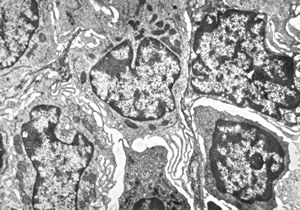

F,68y. | spleen - undefined myelinoid inclusions - clin. susp. leukemia

F,68y. | spleen - myelinoid inclusions - clin. susp. leukemia